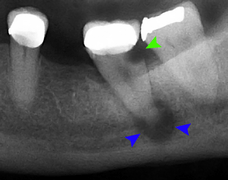

Lateral periodontal abscess (blue arrows) due to a fracture (green arrows)

A periodontal abscess (lateral abscess) is a collection of pus that forms in the gingival crevices, usually as a result of chronic periodontitis where the pockets are pathologically deepened greater than 3mm. A healthy gingival pocket will contain bacteria and some calculus kept in check by the immune system. As the pocket deepens, the balance is disrupted, and an acute inflammatory response results, forming pus. The debris and swelling then disrupt the normal flow of fluids into and out of the pocket, rapidly accelerating the inflammatory cycle. Larger pockets also have a greater likelihood of collecting food debris, creating additional sources of infection.[20]:443

Periodontal abscesses are less common than apical abscesses, but are still frequent. The key difference between the two is that the pulp of the tooth tends to be alive, and will respond normally to pulp tests. However, an untreated periodontal abscess may still cause the pulp to die if it reaches the tooth apex in a periodontic-endodontic lesion. A periodontal abscess can occur as the result of tooth fracture, food packing into a periodontal pocket (with poorly shaped fillings), calculus build-up, and lowered immune responses (such as in diabetes). Periodontal abscess can also occur after periodontal scaling, which causes the gums to tighten around the teeth and trap debris in the pocket.[20]:444–445 Toothache caused by a periodontal abscess is generally deep and throbbing. The oral mucosa covering an early periodontal abscess appears erythematous (red), swollen, shiny, and painful to touch.[21]